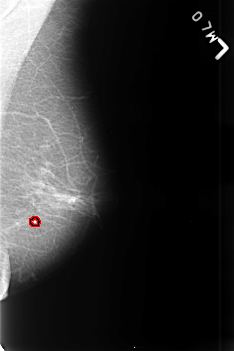

B_3447_1.LEFT_MLO

LEFT_MLO LINES 4552 PIXELS_PER_LINE 3040 BITS_PER_PIXEL 12 RESOLUTION 50 OVERLAY

FILE: B_3447_1.LEFT_MLO.OVERLAY

TOTAL_ABNORMALITIES 1

ABNORMALITY 1

LESION_TYPE CALCIFICATION TYPE ROUND_AND_REGULAR DISTRIBUTION N/A

ASSESSMENT 2

SUBTLETY 4

PATHOLOGY BENIGN_WITHOUT_CALLBACK

TOTAL_OUTLINES 1